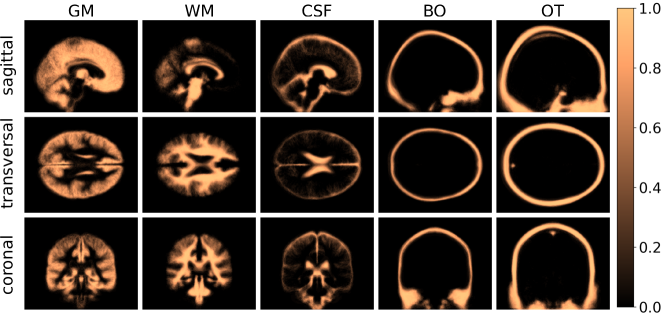

The static component of the atlas distinguishes five main compartments of importance for electrophysiology of the human head: grey matter (GM), white matter (WM), cerebrospinal fluid (CSF), bones (BO) and other soft tissues (OT). Figure 1 depicts the general procedure to calculate the static component of the anatomical atlas.

Figure 1: Main steps necessary to compute the static component of the anatomical atlas. Each image is normalized to a reference image, segmented into the main compartments. Each segment is assigned with the corresponding electrical property and, finally, the statistics of the atlas can be estimated.

Figure 5(a) shows two representative individuals in the segmentation steps to compute the static component of the atlas. The first row contains the original images, the second row contains the normalized images and the third row show the segmented tissues. Figure 5(b) shows the average over the characteristic functions of all individuals and for each segmented tissue. A voxel with a value equal to 1.0 indicates it was classified as the same tissue in all images.

Figure 5: Static atlas computations. (a) Processing steps of two representative individuals of the dataset. The first row shows the original images, the second presents the results of the normalization and the third row the result of the segmentation. GM: red, WM: blue, CSF: green, BO: white, and OT: grey. (b) Average of the characteristic functions 𝝌tsubscript𝝌𝑡\bm{\chi}_{t} for each tissue.